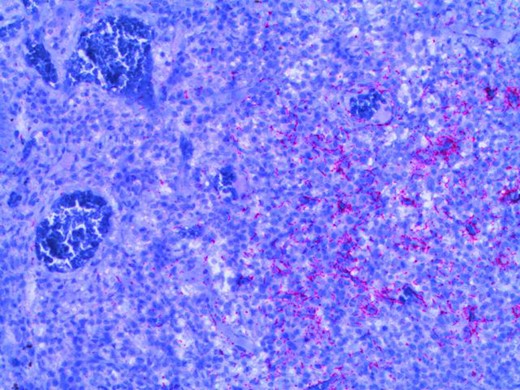

Microscopy photograph from the histological specimen; positive immune-stain for spirochaetes (seen in pink).

Diagnosis may be confirmed histologically using immunostaining for treponemes, or serologically. Serological investigations include: treponemal enzyme immunoassay (EIA) and the Venereal Disease Research Laboratory (VDRL) test [9]. WHO guidelines recommend benzathine penicillin G 2.4 million units once intramuscularly as standard treatment [10]. In the case described, the patient received this treatment and her symptoms improved rapidly. In Australia, as in many other countries, syphilis is a notifiable disease. Referral to a Sexual Health specialist is highly recommended to enable contact tracing and enhanced screening for other associated infections, such as HIV. In this patient’s case, her partner was also found to be affected and required treatment.